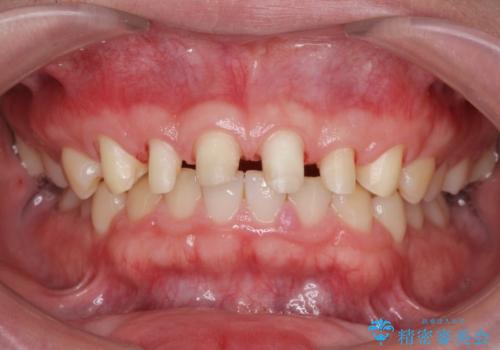

歯周外科を行い、歯ぐきの状態を整えた前歯セラミック治療

- 「前歯の見た目、歯ぐきの腫れを改善したい。」と希望され来院されました。

前歯には接着性の維持装置や、中途半端な形の連結クラウンが装着され、清掃性が悪く歯ぐきの腫れや、歯ぐきの形態の不揃いが認められました。

ただ、白いオールセラミッククラウンを製作・装着するのではなく、将来にわたり安定した状況を獲得するため、歯周外科を行い歯ぐきと周囲の歯槽骨の形態を整えていきます。